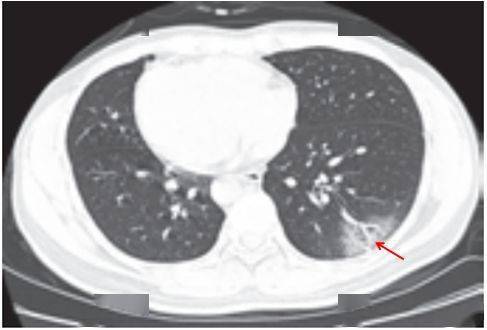

病灶以 肺外围背侧为主,以两肺下叶为著,与胸膜常紧贴,提示新冠肺炎病变多首先侵犯皮层肺组织的细支气管及肺泡上皮, 病灶分布逐步从外周向中央扩展(图 2-1)

图2-1 早期病灶多数分布贴近胸膜( 共4张 )

(三)病灶密度

绝大多数案例出现磨玻璃病灶,最低测得 CT 值约为 - 600Hu(图 2-3),病灶内血管穿行可清晰显示;部分案例磨玻璃病灶与实性病灶共存

根据既往严重急性呼吸综合征(SARS)病理学机制,提示此为肺泡间隔毛细血管扩张充血、肺泡腔内液体渗出和小叶间隔间质水肿

图 2-3早期绝大多数病灶表现为磨玻璃密度( 共4张 )